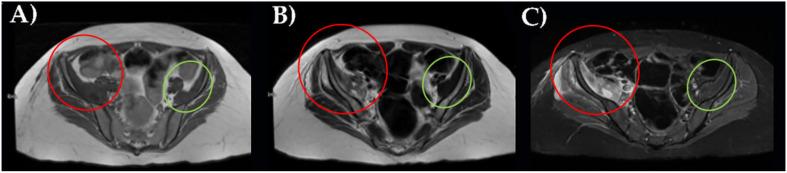

Iliacus muscle hematoma is a very rare condition in rehabilitation wards. A 35-year-old pregnant woman at seven months with cerebellar hematoma with signs of compression underwent a cesarean procedure together with neurosurgical decompression of the posterior cranial fossa procedure. After a period in an intensive unit without any complications, she was admitted to our neurorehabilitation ward and treated with antihypertensive therapy, heparin, and anti-seizure drugs. During a rehabilitation session, after a bed-wheelchair transfer, she was feeling very unwell suffering from severe right leg pain radiating to the mid-face leg. Despite unremarkable physical evidence (skin appearance, temperature, and peripheral arterial pulse in both legs), imaging data (ultrasound, CT, and MRI) confirmed the presence of a right iliac muscle hematoma (IMH). Enoxaparin was immediately stopped, and bed rest was prescribed in an antalgic position with tramadole acetaminophen for pain control. After a few days, the patient felt well and was discharged without any additional symptoms. Our study demonstrates that, when a sudden severe leg pain develops, IMH should be considered in the differential diagnosis. This finding suggests further research and tailored protocols for rehabilitation in patients at high risk for iliacus muscle hematoma.

髂肌血肿在康复病房是一种非常罕见的病症。一名35岁、孕7个月的孕妇患有小脑血肿并有压迫体征,接受了剖宫产手术以及后颅窝神经外科减压手术。在重症监护室度过一段时间且无任何并发症后,她被收治到我们的神经康复病房,并接受了抗高血压治疗、肝素治疗和抗癫痫药物治疗。在一次康复治疗期间,从病床转移至轮椅后,她感觉非常不适,右腿剧痛并放射至小腿中部。尽管体格检查未见异常(双腿皮肤外观、温度及外周动脉搏动),但影像学资料(超声、CT和MRI)证实存在右侧髂肌血肿(IMH)。立即停用依诺肝素,并让患者以止痛体位卧床休息,使用曲马多对乙酰氨基酚控制疼痛。几天后,患者感觉良好,出院时无任何其他症状。我们的研究表明,当突然出现严重腿痛时,鉴别诊断应考虑髂肌血肿。这一发现提示需要针对髂肌血肿高危患者开展进一步研究并制定个性化康复方案。